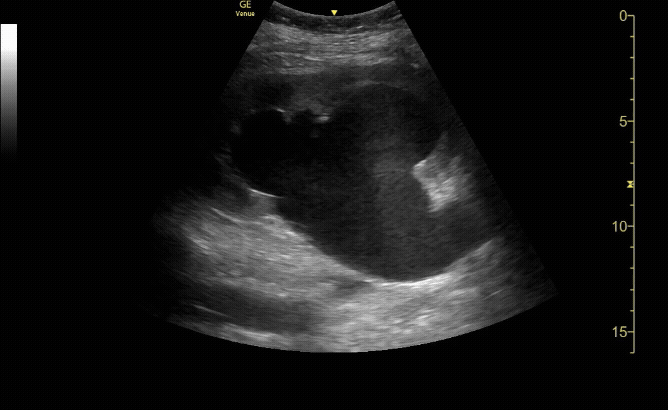

Moderate Hydronephrosis in sagittal( long) view

c/o Evanna Lerouge, MD